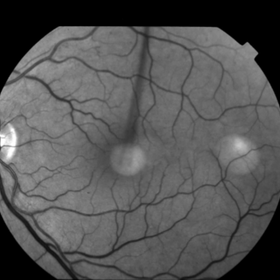

This 68 year old man was referred with a maculopathy but with normal visual acuity. He is thought to have multifocal Best Disease; there is no evidence of inflammation or uveitis and no history of cancer. Macular exam reveals yellow subretinal pigment clumping in each macula, including the foveal area. OCT shows moderate hyper-reflective PED, with no evidence of subretinal fluid or macular edema. Angiography reveals blocking defects due to pigment clumping with no evidence of CNVM.

Multifocal Best Disease Multifocal Best DiseaseJan 31 2015 by Thomas A. Ciulla, MD, MBA, FASRS Angiography reveals blocking defects due to pigment clumping with no evidence of CNVM. Photographer: Charlotte Harris Condition/keywords: adult vitelliform dystrophy, Best disease